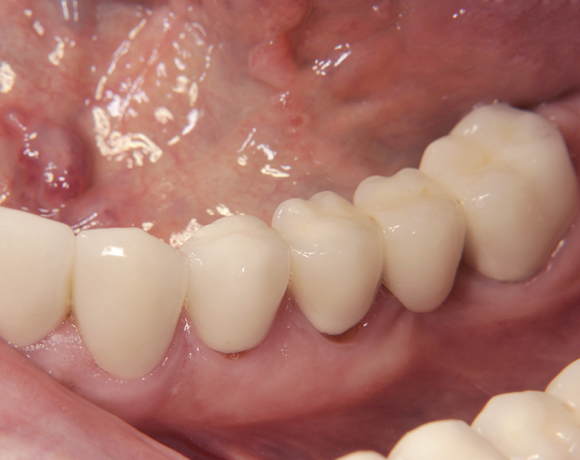

Der vorliegende Patientenfall zeigt eine komplette Neuversorgung der vorhandenen Metallkeramikkronen mit vollkeramischen Restaurationen. Zusätzlich wurde im Oberkiefer die Zahnreihe mit zwei Implantaten, für die fehlenden Molaren, ergänzt. Da keine ausreichende Knochenhöhe vorhanden war wurde ein interner Sinuslift geplant.